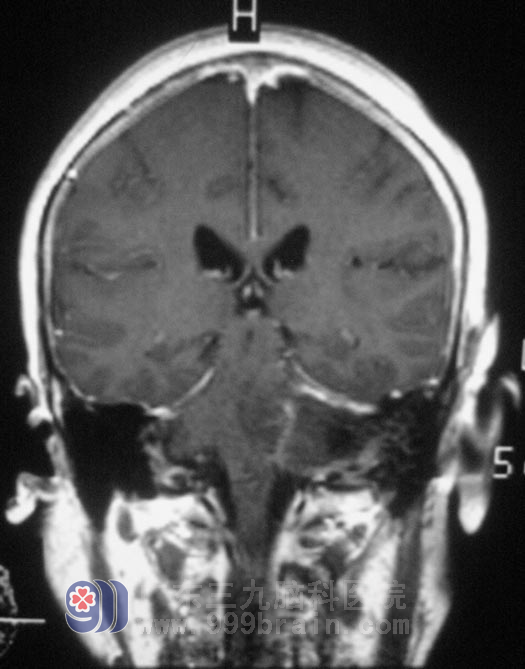

广东三九脑科医院头颅MR检查显示:左侧桥小脑角区示一不规则形囊实性占位性病变,增强后实性部分呈不均匀明显强化,囊性部分未见强化,侧面听神经增粗强化,范围约为3.6cm×4.2cm×3.7cm,周围示轻微水肿,桥脑、延髓,左侧桥臂及左侧小脑半球受压变形、移位,四脑室受压变窄,左侧内听道明显扩大。检查左耳失聪,左侧额纹、鼻唇沟较右侧轻微变浅,伸舌左偏。